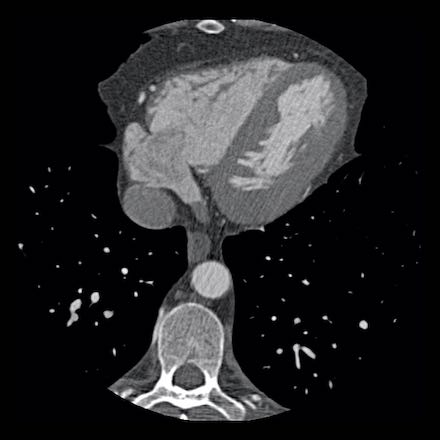

Same patient. First, study the CTA image.

How would you describe the findings?

The coronal image shows a central low-attenuation area around the lumen

of the LAD.

This low-attenuation area is surrounded by a higher attenuation

area.

This finding is the earlier discussed napkin-ring sign, which is a high-risk

plaque feature.

This patient classifies as CAD-RADS 4A/P1/HRP.